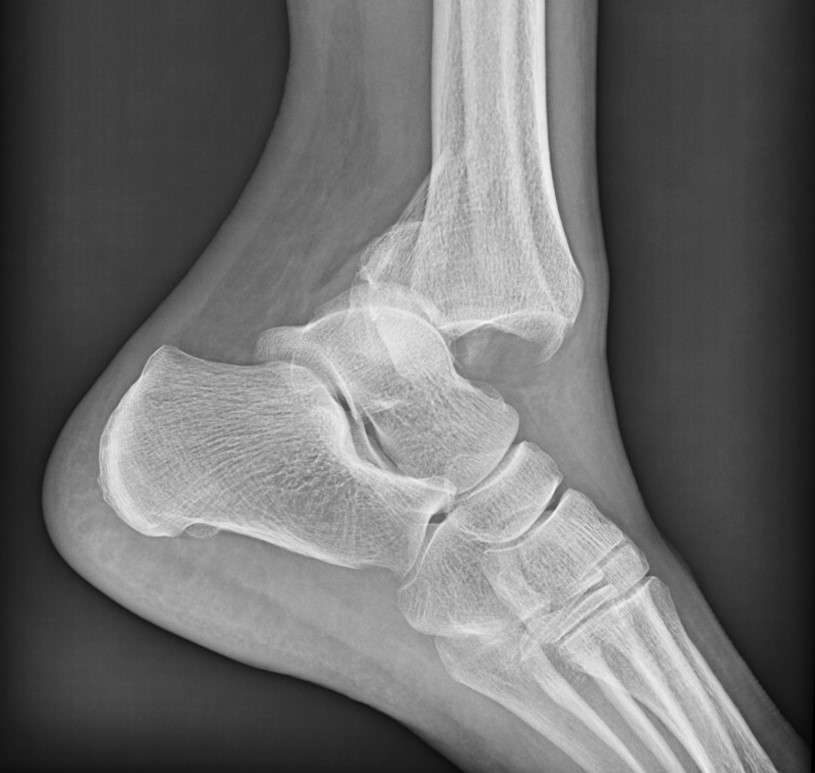

There are three bones in the ankle, simply called as tibia (shinbone), the fibula (outer lower leg bone), and the talus (small foot bone). These elements in the ankle not only help it move, but they also work together to promote stability. A broken ankle is most often from a turning, twisting, or rolling injury. Although bones and joints are the strongest organs of the body, if some pressure exceeds their strength, then they can be fractured.

The ankle fractures can be stable, displaced, open, or complex, depending on the severity. Ankle fractures often go unnoticed for various reasons: the pain reduces after a few days, home remedies seem to work well, or people are afraid of surgery. Some individuals also delay seeking proper medical care due to financial concerns, lack of awareness, or uncertainty about where to find reliable Ankle Fracture treatment in Lahore.